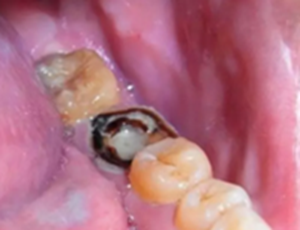

嚴(yán)重蛀牙:牙冠遭到嚴(yán)重破壞的,而且牙根或牙周情況無法做樁冠修復(fù)的。

為什么有些牙齒不能拔?拔牙無小事!